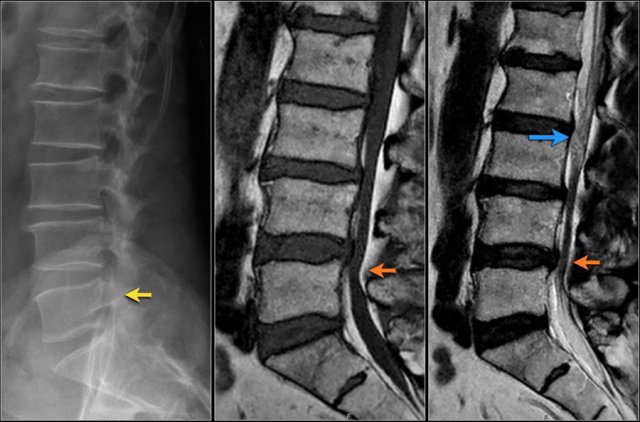

Notice the diffuse narrowing of the lumbar spinal canal.

It is best seen on the MR-images, but can already be suspected on the radiograph, because the pedicles are very short.

You may have to enlarge the image to appreciate this.

On the axial T2W-images you can see, that there is no CSF visible surrounding the nerve roots.

This means that there is a severe spinal stenosis.

Here another example of spinal stenosis.

Again on the radiograph you can suspect congenital narrowing.

Usually a small hernia or bulging is enough to cause nerve compression in these patients.

On the axial T2W-images a severe spinal stenosis is seen.

Notice the short pedicles in combination with facet arthrosis and flavum hypertrophy.